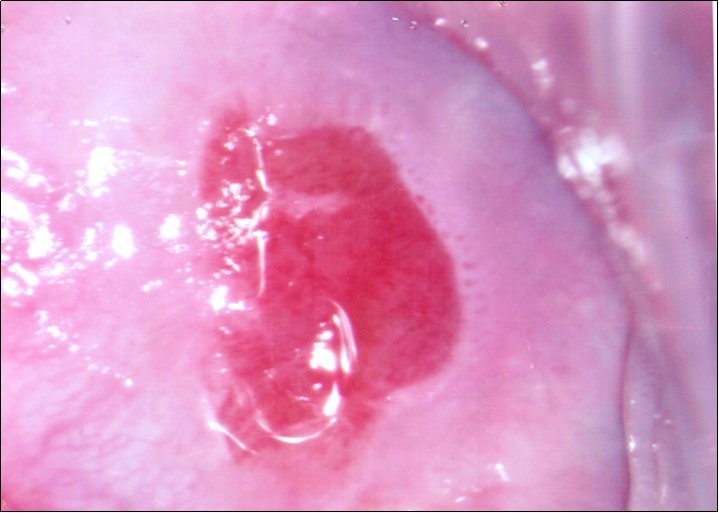

Repeat colposcopy was performed after 6 weeks. This revealed a small ulcerated area at the site of previous biopsy with rolled healing edges, and a separate small ulcer at the 12 o’clock position. (Figure 2a, Figure 2b, Figure 2c) Careful inspection of the buccal mucosa revealed similar ulcers in the left buccal region. (Figure 3)

Figure 2b.Repeat colposcopy (high magnification)

Repeat colposcopy (high magnification)

Figure 2c.Repeat colposcopy (high magnification)